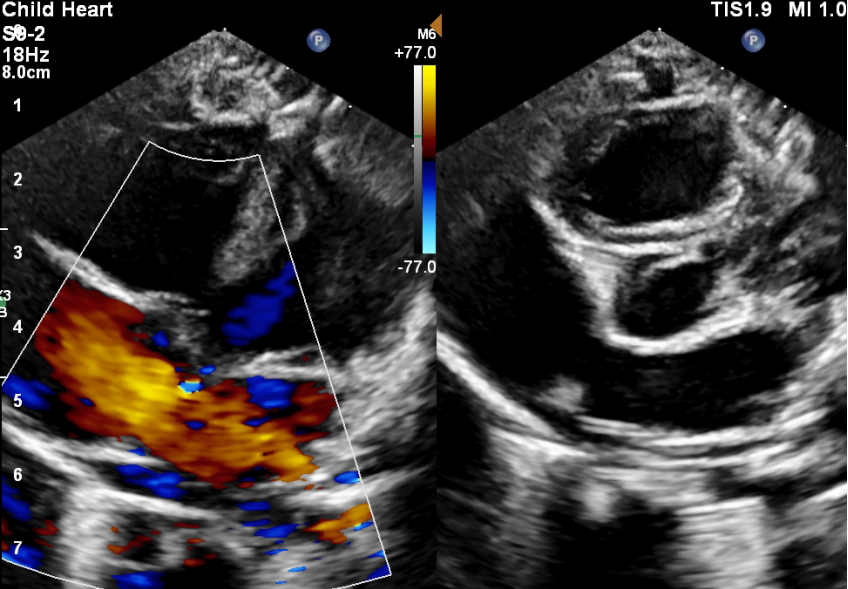

在赵源的耐心解释和坚持下,欣欣妈妈最终还是带宝宝来到超声医学科进行了心脏彩超检查,检查发现:先天性心脏病 房间隔缺损(继发孔型)(如下图)。

目前绝大多数房缺根据临床表现及超声心动图即可确诊。心脏彩超检查是目前最简单直接的无创检查手段,可以发现房间隔缺损的类型、位置以及大小。并可以测量肺动脉压力评估有无肺动脉高压,评估右心的大小及功能。